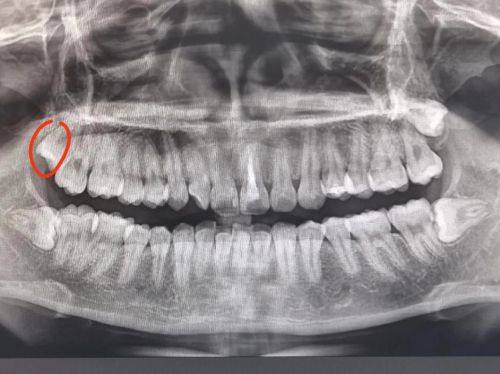

18. 口腔CT:300 - 800元